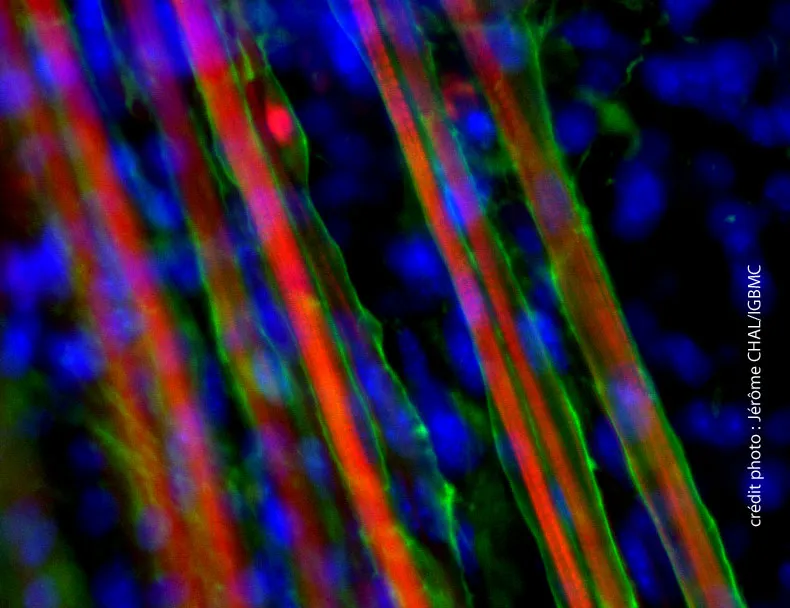

Une méthode pour obtenir des fibres musculaires et des cellules souches satellites à partir de cellules souches embryonnaires a été mise au point par une équipe soutenue par l’AFM-Téléthon.